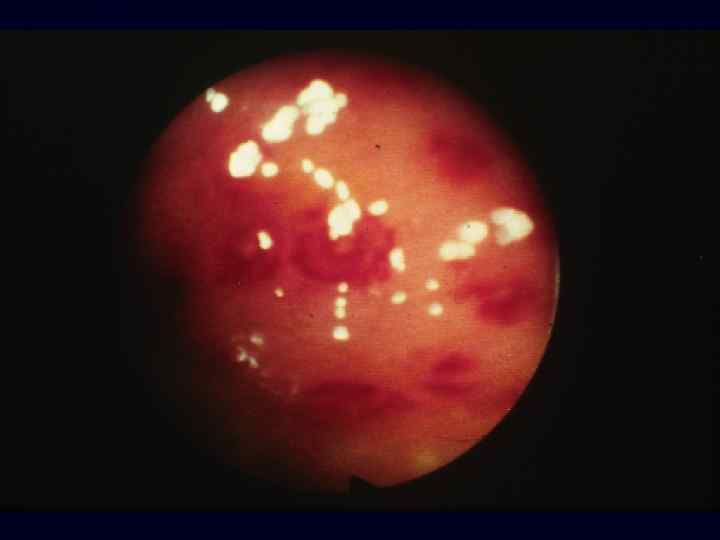

Саркома Капоши